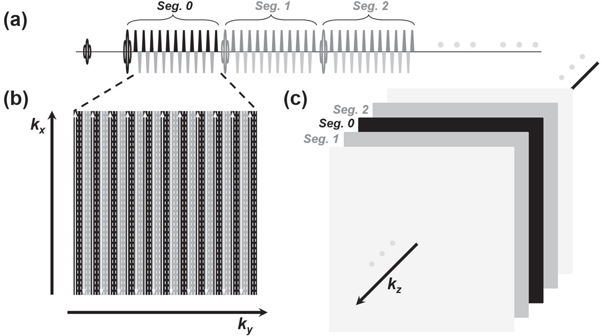

Separate off-resonance and T2 (SORT) view-ordering strategy (Mugler 1999) was applied in the 3D GRASE sequence, as demonstrated in figure 1. GRASE is one of the fastest readout sequences by combining the speed benefits of EPI and FSE (figure 1(a)). For the SORT, the basic idea is to arrange echo signals from EPI and FSE echo trains respectively to different phase-encoding dimensions (i.e. ky and kz). k-space lines from each EPI echo train of GRASE are arranged along ky (figure 1(b)). In the present design, three GRASE shots were utilized to complete each 2D kx–ky partition in an interleaved fashion. In other words, all echo signals from each FSE refocusing segment were bundled to fill the k-space lines in correspond to a single kz (in head-foot, or slice direction) partition. Bundles of echo signals from different FSE segments were respectively filled in a center-out way along kz (figure 1(c)). Therefore, if a scanning protocol should be without slice oversampling and kz partial Fourier settings, the number of FSE segments would be set exactly equal to the number of slice (or equivalently say, kz). Notably, a segmented interleaved kz acquisition could be applied by cutting the FSE echo train in half in each GRASE shot and repeating all previously performed acquisition once again with a different set of shifted slice (i.e. kz) phase-encodings, although the scan duration was doubled with this segmented kz design.

Figure 1. Schematic 3D GRASE sequence with SORT view-ordering design (a) a GRASE sequence is comprised of EPI trains inserted into FSE focusing segments (only the first three refocusing segments, segs. 0, 1, and 2, are displayed for simplicity). Gradient blocks other than the EPI bipolar trains are omitted in this illustration. (b) The kx–ky partition of a 3D k-space. The EPI echo lines are filled in this partition in an interleaved fashion. The solid arrow lines signify the sampled k-space lines from the above EPI echo train. The dash lines are to be filled with the same segments from subsequent GRASE shots. (c) Each FSE refocusing segment is responsible for a partition at different kz, and all the segments are arranged in a center-out fashion along kz for k-space filling.